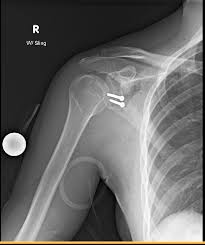

שבר בראש הזרוע